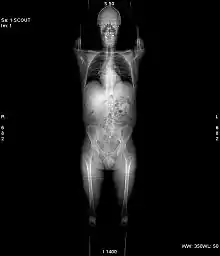

X-ray computed tomography operates by using an X-ray generator that rotates around the object; X-ray detectors are positioned on the opposite side of the circle from the X-ray source.

In conventional CT machines, an X-ray tube and detector are physically rotated behind a circular shroud (see the image above right). An alternative, short lived design, known as electron beam tomography (EBT), used electromagnetic deflection of an electron beam within a very large conical X-ray tube and a stationary array of detectors to achieve very high temporal resolution, for imaging of rapidly moving structures, for example the coronary arteries. Systems with a very large number of detector rows, such that the z-axis coverage is comparable to the xy-axis coverage are often termed cone beam CT, due to the shape of the X-ray beam (strictly, the beam is pyramidal in shape, rather than conical). Cone-beam CT is commonly found in medical fluoroscopy equipment; by rotating the fluoroscope around the patient, a geometry similar to CT can be obtained, and by treating the 2D X-ray detector in a manner similar to a CT detector with a massive number of rows, it is possible to reconstruct a 3D volume from a single rotation using suitable software.

Spiral computed tomography, or helical computed tomography, is a computed tomography (CT) technology in which the source and detector travel along a helical path relative to the object. Typical implementations involve moving the patient couch through the bore of the scanner whilst the gantry rotates. Spiral CT can achieve improved image resolution for a given radiation dose, compared to individual slice acquisition. Most modern hospitals currently use spiral CT scanners.

Initial machines would rotate the X-ray source and detectors around a stationary object. Following a complete rotation, the object would be moved along its axis, and the next rotation started. Newer machines permitted continuous rotation with the object to be imaged slowly and smoothly slid through the X-ray ring. These are called helical or spiral CT machines. A subsequent development of helical CT was multi-slice (or multi-detector) CT; instead of a single row of detectors, multiple rows of detectors are used effectively capturing multiple cross-sections simultaneously.